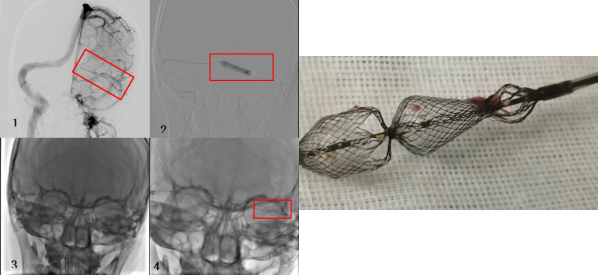

2024年新疆医科大学第一附属医院神经外科中心周刊如期与大家再次见面。新疆医科大学第一附属医院神经外二科,脊髓、脑血管病组,自1994年开始神经介入诊治工作率先在西北开展动脉瘤、动静脉畸形、颅内外动静脉畸形、脊髓动静脉畸形.缺血性脑卒中各种血管内治疗等介入治疗。近期开展新型静脉窦取栓装置取栓装置GCP临床实验器械,并开展工作,报道最新病例,与同道共享。

诊治经过

术后

术后1周患者专科查体:神志清,对答切题,定位定向准确,双瞳等大、等圆,光反射灵敏,四肢肌力肌张力正常。术后脑脊液压力:150mmH₂O。

脑静脉窦血栓患者选择血管内介入治疗的基本原则是“解危救难”,是对抗凝等保守治疗的有力补充。也就是病情急剧凶险,难以等待观察抗凝等保守治疗的效果,如不紧急实施介入治疗,继续等待可能出现灾难性后果;或在积极抗凝等治疗一段时间的情况下,病情仍然进展加重,或大范围脑实质损害无变化,如不实施介入治疗,则存在病情恶化的风险。还有就是,在抗凝治疗下的慢性脑静脉窦血栓患者,当引发严重症状时,介入治疗常可缓解症状。

慢性脑静脉窦血栓介入治疗的主要策略是血管成形和支架植入,血栓抽吸会在少数情况下应用到。首先是球囊扩张,如果管腔恢复好,静脉窦引流通畅满意,则可不植入支架;如果球囊扩张后管腔恢不佳,静脉窦引流无明显改善,则需植入支架。